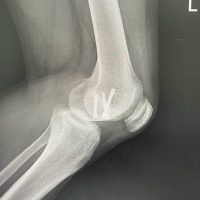

Figure 4: Anteroposterior and lateral radiographs at 3 months showing well-healed internal fixation of periprosthetic fracture with implants in situ, showing well-taken vascularized fibula graft (a and b). Intra-operative clinical image showing harvest of vascularized fibula graft from [L] leg (c) (Figure 4C).